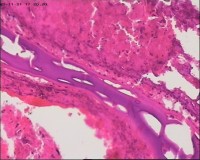

性别

女

年龄

20岁

停经3月,阴道不规则流血7天。

宫刮物

灰白灰红碎组织一堆,大小为7*6*1cm,部分组织呈水泡状

水肿的绒毛和蜕膜,没看到增生的滋养细胞。必要时可做IHC除外部分葡萄胎,并结合临床HCG。

考虑葡萄胎